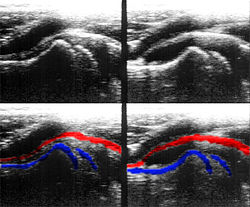

Die Aussagekraft der Sonografie kann erheblich durch die Anwendung des Doppler-Effekts erhöht werden. Man unterscheidet eindimensionale Verfahren (Pulsed-Wave-Doppler, Continuous-Wave-Doppler, auch als D-mode bezeichnet) von zweidimensionalen, farbkodierten Anwendungen (Farbdoppler – F-mode). Die Kombination B-Bild mit Pulsed-Wave-Doppler (PW-Doppler) nennt man auch Duplex.[4]

Doppler-Verfahren werden benutzt zur Bestimmung von Blutfluss-Geschwindigkeiten, zur Entdeckung und Beurteilung von Herz(klappen)fehlern, Verengungen (Stenosen), Verschlüssen oder Kurzschlussverbindungen (Shunts).

Bei der farbkodierten Doppler-Sonografie wird für einen großen Bereich eines konventionellen Ultraschallbildes (Color-Window) die örtliche Doppler-Frequenz (= mittlere Flussgeschwindigkeit) und deren Schwankungsbreite bestimmt. Damit möchte man die Turbulenz der Strömung abschätzen. Aufgrund der statistischen Bewegungen der Streuteilchen ist die Schwankungsbreite der Fließgeschwindigkeit jedoch stets größer als die Turbulenz. Das Ergebnis wird in Falschfarben auf dem B-Bild überlagert, also in Farbtönen von rot und blau für verschiedene Blutgeschwindigkeit und grün für Turbulenz. Hierbei steht üblicherweise die Farbe Rot für Bewegung auf den Schallkopf zu, während mit blauen Farbtönen Flüsse weg von der Sonde codiert werden. Bereiche der Geschwindigkeit 0 werden durch die Elektronik unterdrückt.